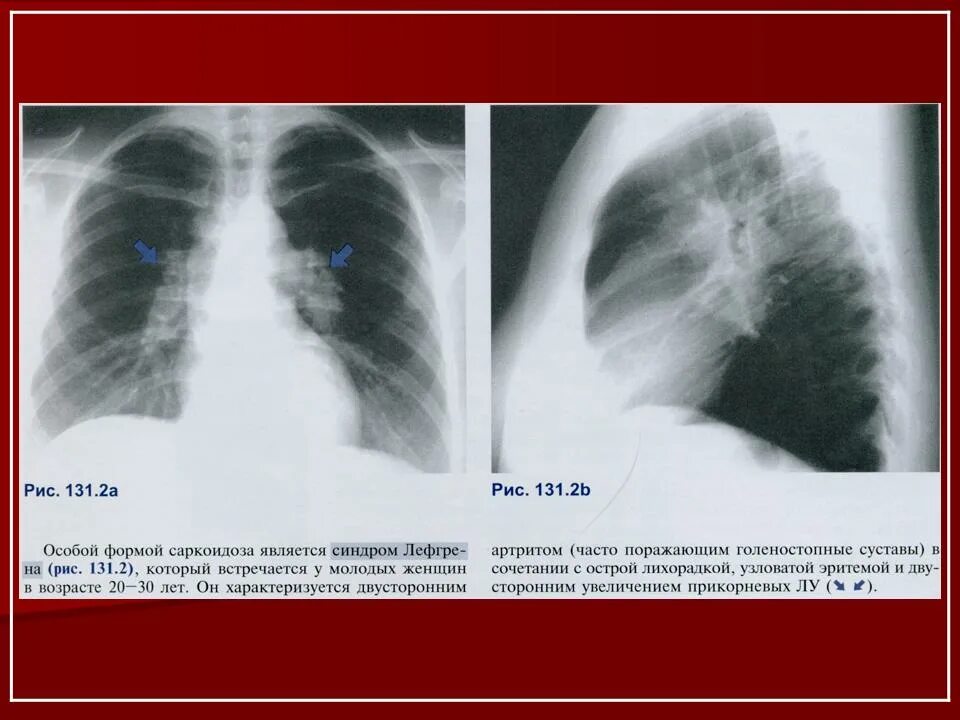

Саркоидоз 1